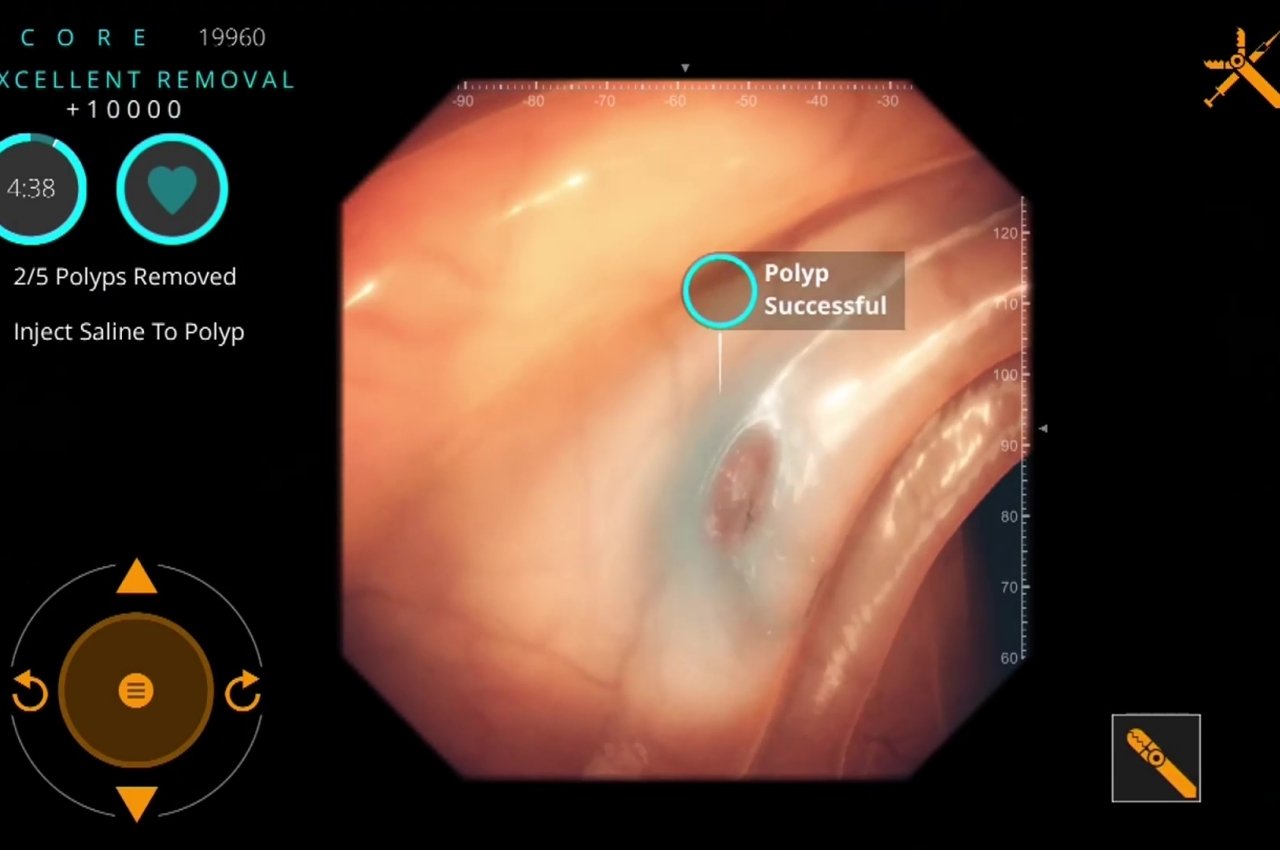

Il Metaverse riguarda il divertimento e i giochi non è necessariamente una cosa negativa, specialmente se fatto con moderazione. In effetti, giocare non è una brutta cosa, nonostante le connotazioni e i pregiudizi che circondano anche solo la parola. Le persone hanno imparato molto tempo fa che i giochi, o in particolare le attività ludiche, possono essere utili per l'apprendimento e l'adattamento a cose nuove. Può anche aiutare le persone a far fronte a traumi o stress.

La gamification, o l'applicazione del pensiero di gioco e delle meccaniche di gioco ad attività non di gioco, esiste ormai da anni. Dalle classifiche ai livelli ai punteggi più alti, queste piccole cose possono dare un senso di realizzazione che rafforza le nuove conoscenze che abbiamo appena acquisito. E poiché le stesse tecnologie utilizzate per creare giochi creano anche il Metaverse, l'intersezione tra la ludicizzazione e il Metaverse è praticamente nella borsa.

Nasa, ad esempio, ha arruolato uno sviluppatore di giochi specializzato nell'utilizzo di giochi per formare persone, in particolare medici, nella diagnosi e nel trattamento di diverse condizioni. L'idea è quella di addestrare gli astronauti ad avere sufficienti conoscenze mediche in caso di emergenza, nel caso in cui sia il medico di bordo che necessita di cure. Questi strumenti educativi hanno tutti i tratti distintivi dei tipici giochi per dispositivi mobili, tranne per il fatto che ti allena con abilità serie e salvavita piuttosto che semplicemente schiacciare lo schermo per ottenere uccisioni.

Progettista: Livello Es